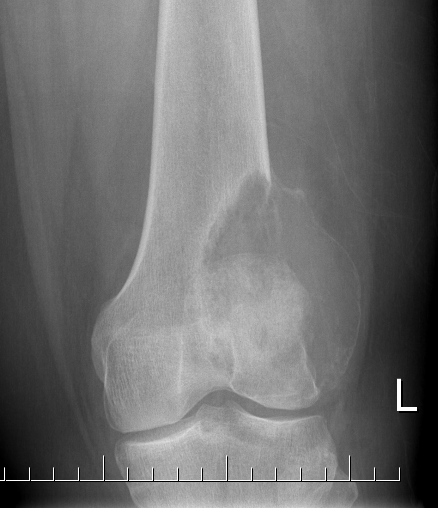

X-ray

Eccentric, sharply demarcated lytic lesion

- no sclerosis around lesion

- narrow zone of transition

- metaphysis, extending into epiphysis

- no mineralization